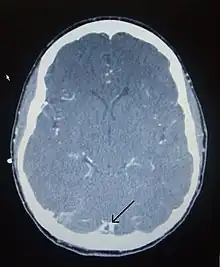

CT venogram showing a filling defect in the sagittal sinus (black arrow)

There are various neuroimaging investigations that may detect cerebral sinus thrombosis. Cerebral edema and venous infarction may be apparent on any modality, but for the detection of the thrombus itself, the most commonly used tests are computed tomography (CT) and magnetic resonance imaging (MRI), both using various types of radiocontrast to perform a venogram and visualise the veins around the brain.[3]

Computed tomography, with radiocontrast in the venous phase (CT venography or CTV), has a detection rate that in some regards exceeds that of MRI. The test involves injection into a vein (usually in the arm) of a radioopaque substance, and time is allowed for the bloodstream to carry it to the cerebral veins – at which point the scan is performed. It has a sensitivity of 75–100% (it detects 75–100% of all clots present), and a specificity of 81–100% (it would be incorrectly positive in 0–19%). In the first two weeks, the "empty delta sign" may be observed (in later stages, this sign may disappear).[11] The empty delta sign is characterized by enhancement of the dural wall without intra-sinus enhancement.[6]